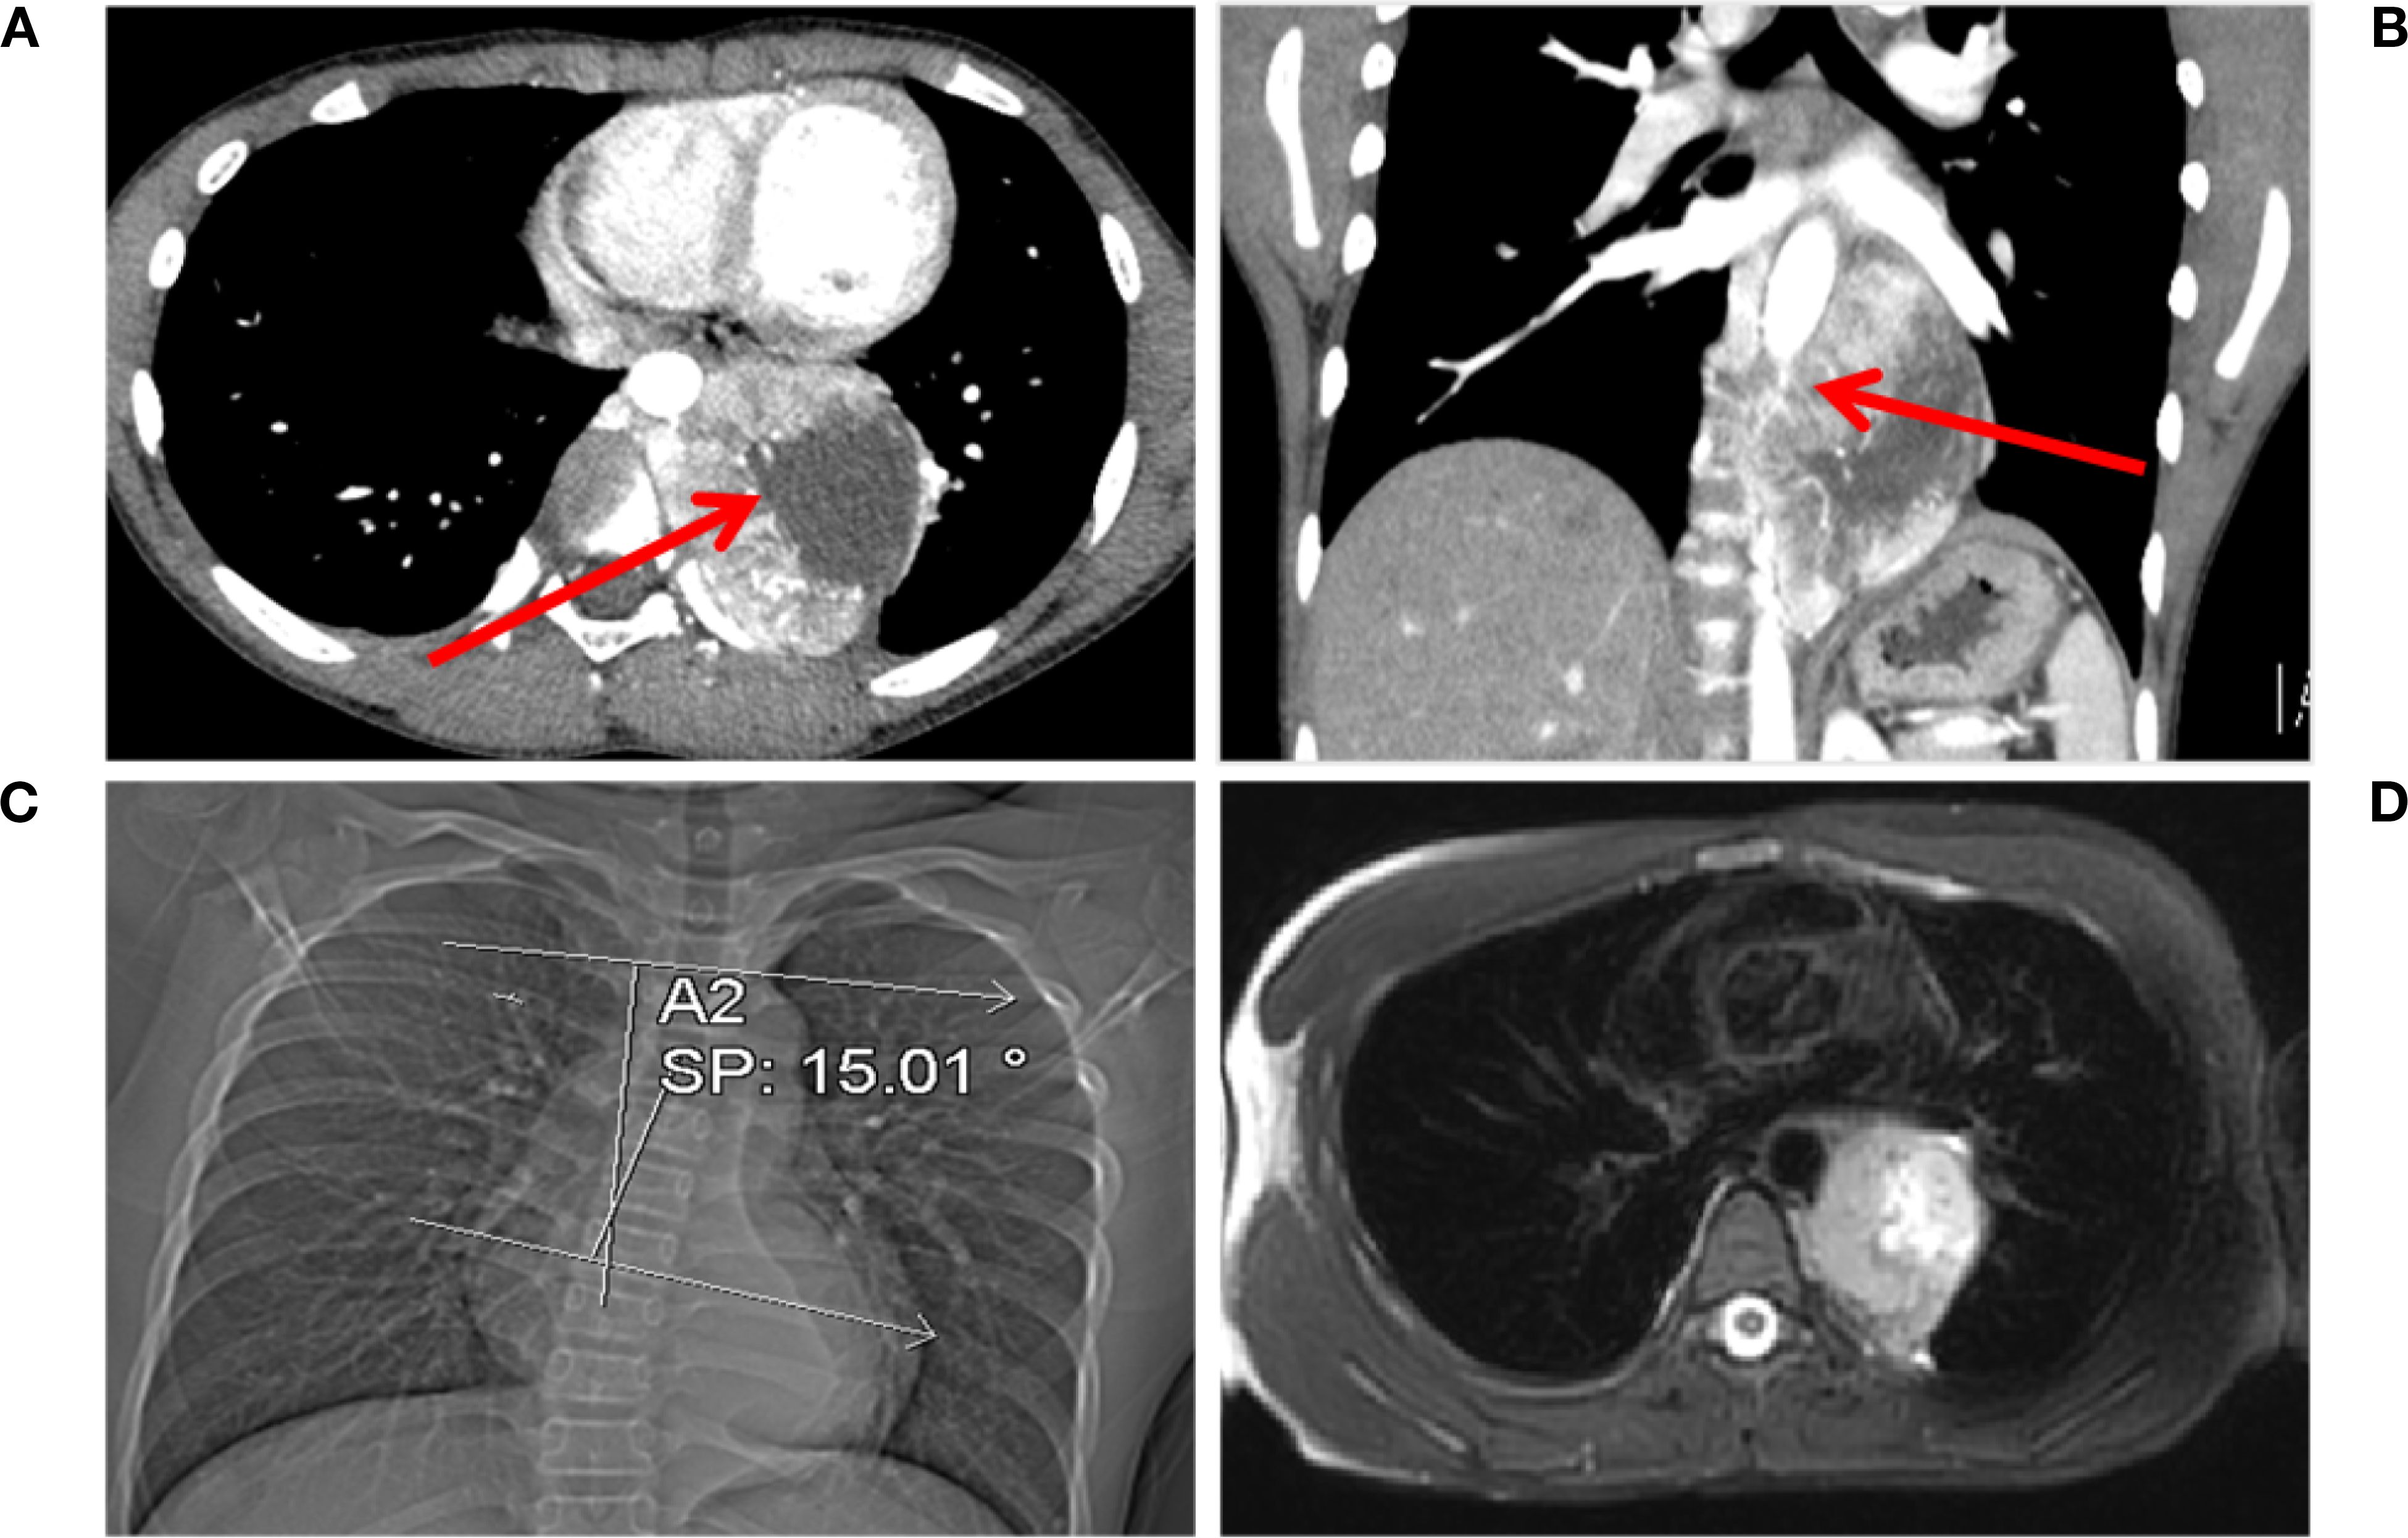

The mass, measuring 8.0 × 5.6 × 7.2 cm, exhibits cystic necrosis and is heterogeneously enhanced (Figure 1A). The arterial feeders originate from the descending aorta. The mass demonstrates circumferential aortic encasement, accompanied by spinal column displacement (Figure 1B). This results in the induction of a Cobb angle scoliosis measuring 15.01° (Figure 1C). The MRI scan revealed a lesion that was T1-hypointense and T2-hyperintense, with clearly defined margins. Importantly, there was no evidence of involvement with the foramina or spinal canal (Figure 1D). Enhanced chest CT and MRI scans clearly showed the extent of the lesion and its vascular relationships. No other suspicious lesions were identified in the chest or abdomen.

Figure 1. Chest CT and MRI findings. (A) Multiple vascular shadows are visible in the arterial phase, accompanied by an irregularly enhanced mass. Necrosis is present within the tumor, as indicated by the red arrow. (B) The tumor encircles the aorta (indicated by the red arrow) in the coronal view. (C) The tumor compresses the spine, causing scoliosis (Cobb angle: 15.01°). (D) T2-hyperintense lesion with clear margins is observed, with no involvement of the intervertebral foramen or spinal cord.